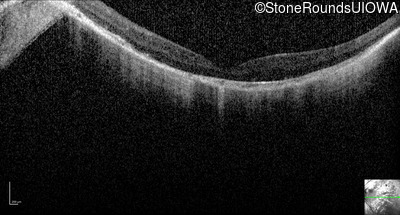

Optical Coherence Tomography - Right - 20/200 -2

Exemplar / OCT Stack